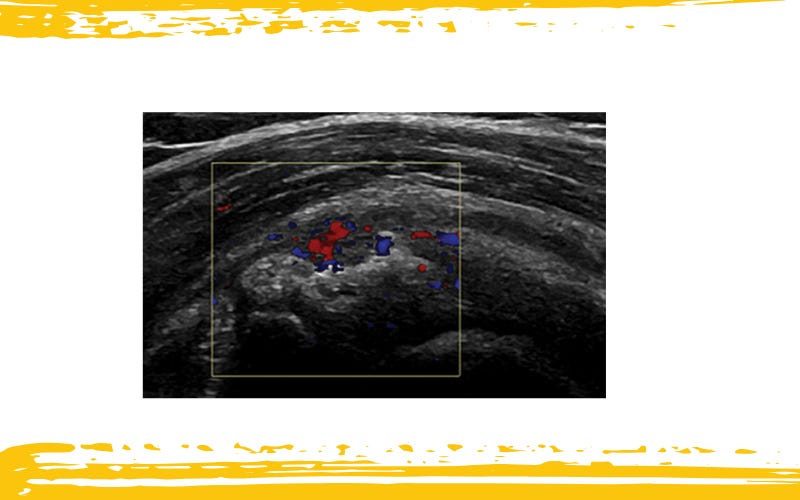

Tendinosis calcificante con pérdida de la interfaz de la bursa subdeltoidea-subacromial, sombra acústica y neovascularización.